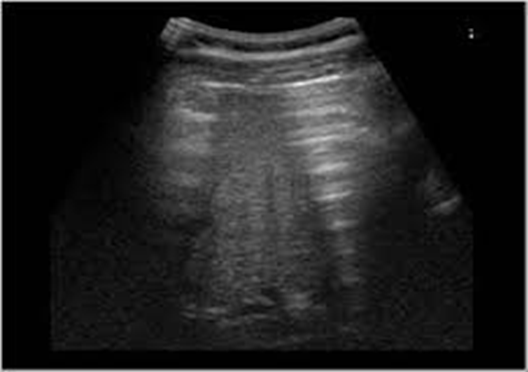

•Kết quả siêu âm: Hình ảnh hơi tự do ổ bụng (dấu hiệu rèm cửa vị trí gan phải) kèm dịch ổ bụng lượng ít (vị trí khoang Morrison và vùng hạ vị).